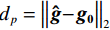

${{\boldsymbol{f}}_{{\rm{res}}}}$ 是重建图像的向量表示,${{\boldsymbol{f}}_{{\rm{truth}}}}$ 是真实图像的向量表示,N为向量长度。$$ {{\rm{RMSE}}\left( {{{\boldsymbol{f}}_{{\rm{rec}}}},{{\boldsymbol{f}}_{{\rm{truth}}}}} \right) = \frac{{{{\big\| {{{\boldsymbol{f}}_{{\rm{rec}}}} - {{\boldsymbol{f}}_{{\rm{truth}}}}} \big\|}_2}}}{{\sqrt N }}} 。 $$ (17) 对于Shepp-Logan模体和FORBILD模体重建来说,当RTV最小化算法分别迭代到200次和300次左右时,其各自的RMSE已经小于10-4,符合该实验定量分析正确性的标准。而从重建结果来看,如图2和图3所示,其中(a)图是Shepp-Logan和FORBILD仿真模型图像;(b)是实现收敛的重建图像;(c)是(a)、(b)两幅图像中心线波形的比较。从图2和图3可见(a)、(b)两幅图几乎完全一样,难以分辨彼此。从(c)图可见(a)、(b)两幅图的中心线波形几乎完全重合。对重建图像和中心线波形的观察表明,该算法实现了高精度重建,符合该实验定性观察正确性的标准。

总的来说,无论是从重建结果的定性观察,还是重建图像的RMSE小于

${10^{ - 4}}$ 来看,都可以说明该实验的正确性研究是成功的,从而说明所构建的模型及代码实现是正确的。3.1.3 RTV最小化重建算法的收敛性评估